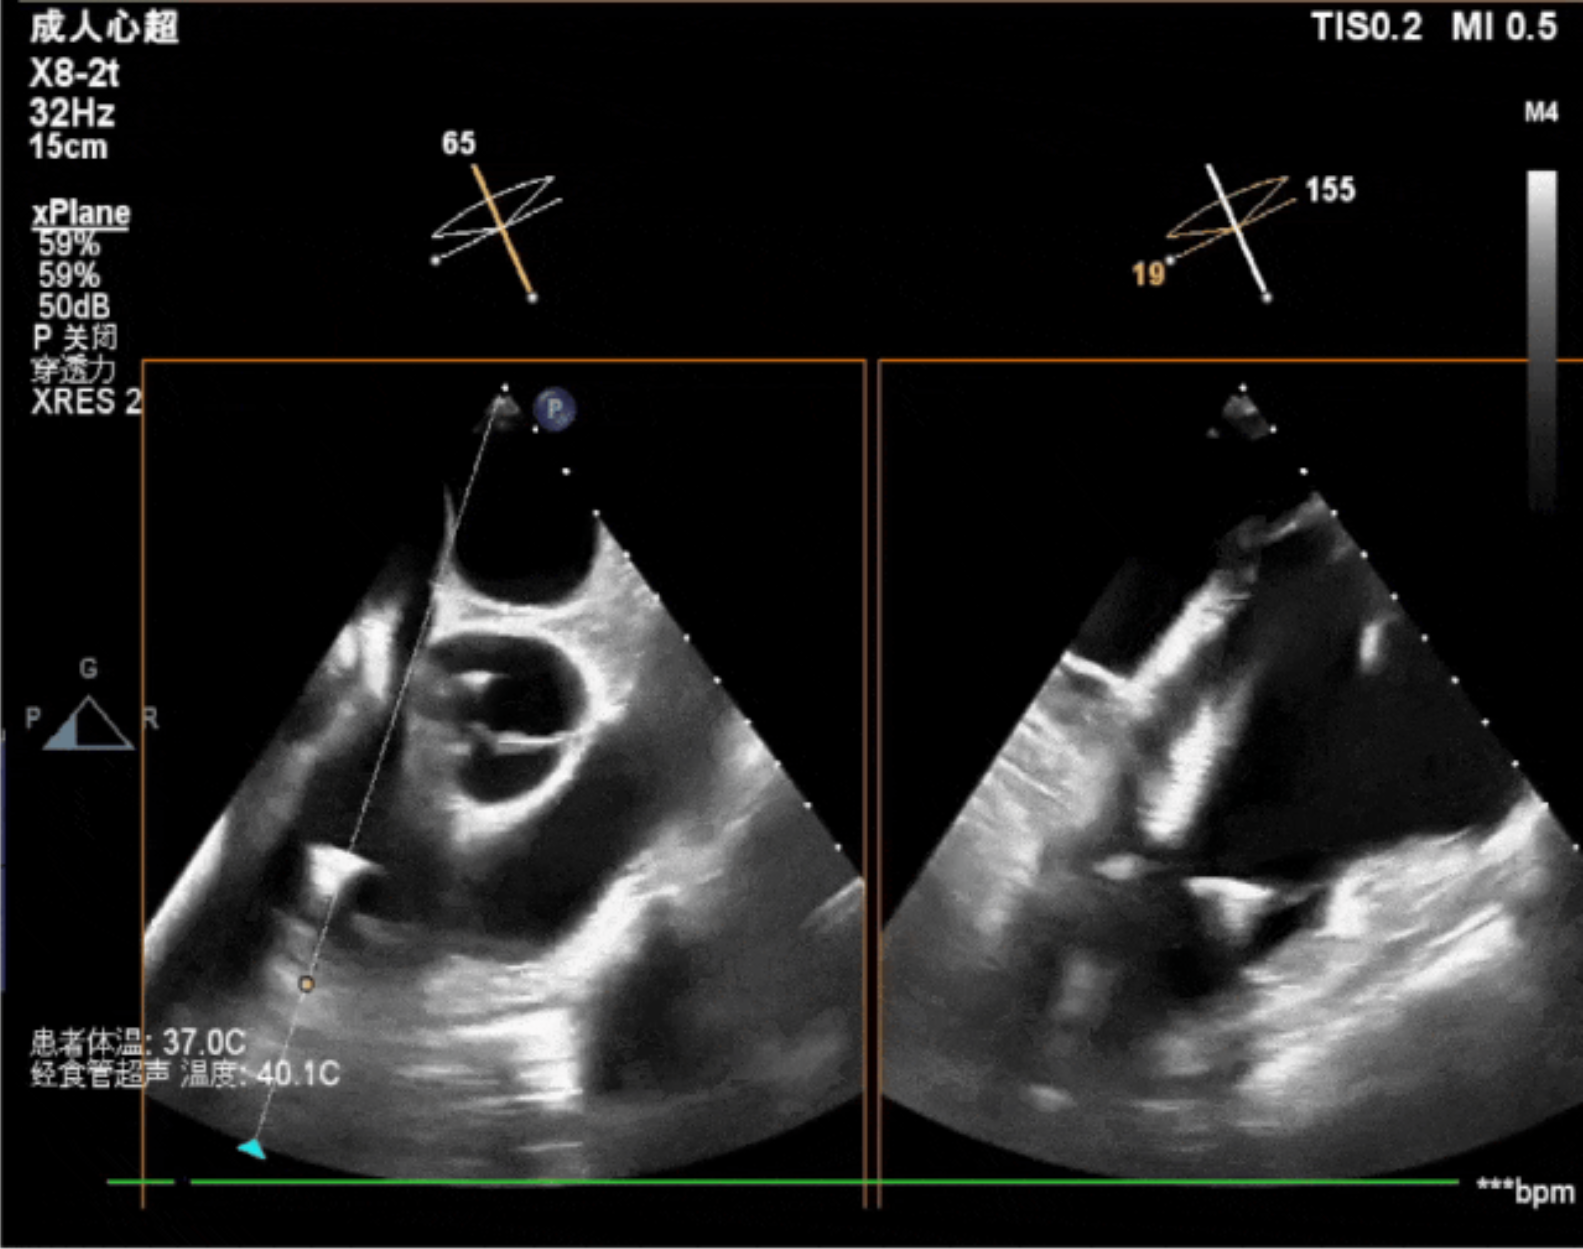

術中經食道超聲輔助下可見LuX-Valve Plus夾持件抓捕瓣葉狀態良好,夾持件在位,室間隔錨定位置良好,假體瓣膜整體錨定狀態穩固。

術后即刻經食道超聲可見,三尖瓣假體瓣膜位置合適,牛心包瓣葉運動狀態良好,開閉正常,瓣周及瓣葉對合緣處未見明顯返流,心電圖及心包狀態較術前無明顯變化。

本次直播手術中,手術團隊在超聲與DSA等多維影像手段的支持下,精準嫻熟的完成LuX-Valve Plus瓣膜的植入,器械操作時間僅為30分鐘,瓣膜植入后術中即刻三尖瓣返流消失,多普勒超聲下無明顯瓣周漏或中心性返流,肺動脈壓正常,平均跨瓣壓差僅為1mmHg,人工瓣膜運動正常,術后1小時內該患者即安返病房。

今天我們見證了一臺嫻熟、優雅且迅速的經導管三尖瓣置換手術,我們可以看到的是,手術完成后的三尖瓣超聲指標非常完美,值得一提的是,經食道超聲技術在整臺手術中有著非常重要的作用,我們可以用幾個簡單的切面精準的指引LuX-Valve Plus的植入,相信在未來,超聲在三尖瓣介入置換圍術期中將有著更重要且成熟的應用。